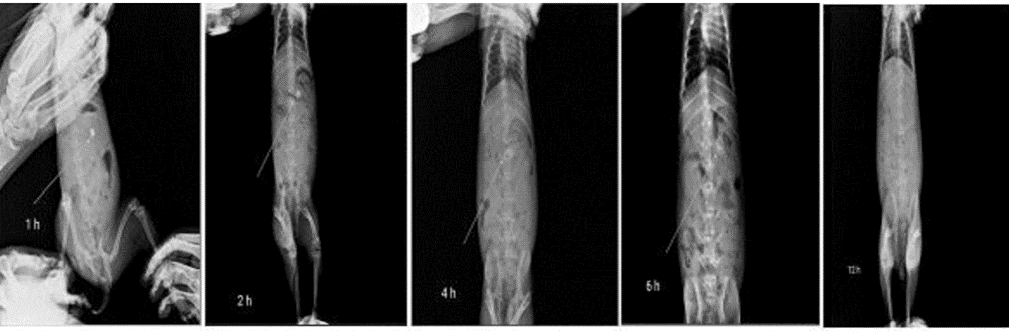

In vivo buoyancy study by using X ray

The tablets are prepared by replacing some quantity of drug with barium sulfate. The in vivo buoyancy study conducted using healthy albino rabbits. Prepared optimized tablet containing barium sulphate administered to rabbits. X ray was taken at intervals of 1, 2, 4, 6 and 12 h [25].

Fig. 6: X ray pictures of tablet at 1, 2, 4, 6 and 12 h

In vivo tablet behavior is shown in X-ray picture of fig. 6 from this it was clear that tablet float intact more then 6h and less then12h.